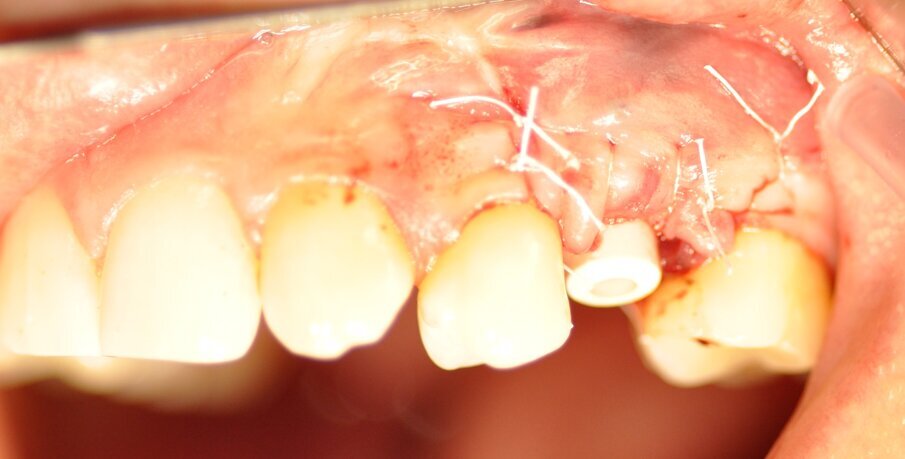

La paziente presentava un primo premolare superiore sinistro non recuperabile. La CBCT mostra la situazione iniziale (Fig. 1). Si noti quella che appare come una grande fenestrazione buccale nell’area della resezione radicolare (Fig. 2). Il dente fratturato è stato estratto (Figg. 3, 4). Lo scollamento del lembo di accesso rivela la fenestrazione buccale (Fig. 5). L’osteotomia è stata preparata secondo il protocollo di fresatura di Neoss ProActive Edge (Fig. 6). Successivamente viene posizionato un impianto Neoss ProActive Edge Ø 5.0 × 13 mm (Fig. 7). L’impianto è stato posizionato in una situazione di disponibilità ossea molto limitata e densità ossea media (Fig. 8). Nonostante le limitazioni dovute alla condizione ossea, è stata raggiunta una buona stabilità primaria. È stato utilizzato un torque di inserimento di 20 Ncm, l’ISQ è risultato in un range di 70/77. Per correggere la fenestrazione buccale è stato eseguito un innesto con particolato osseo di origine porcina (Fig. 9). L’innesto osseo è stato coperto con una membrana di collagene riassorbibile (Fig. 10). Il lembo mucoso è stato suturato attorno al pilastro di guarigione in PEEK, consentendo la guarigione in una sola fase (Fig. 11).